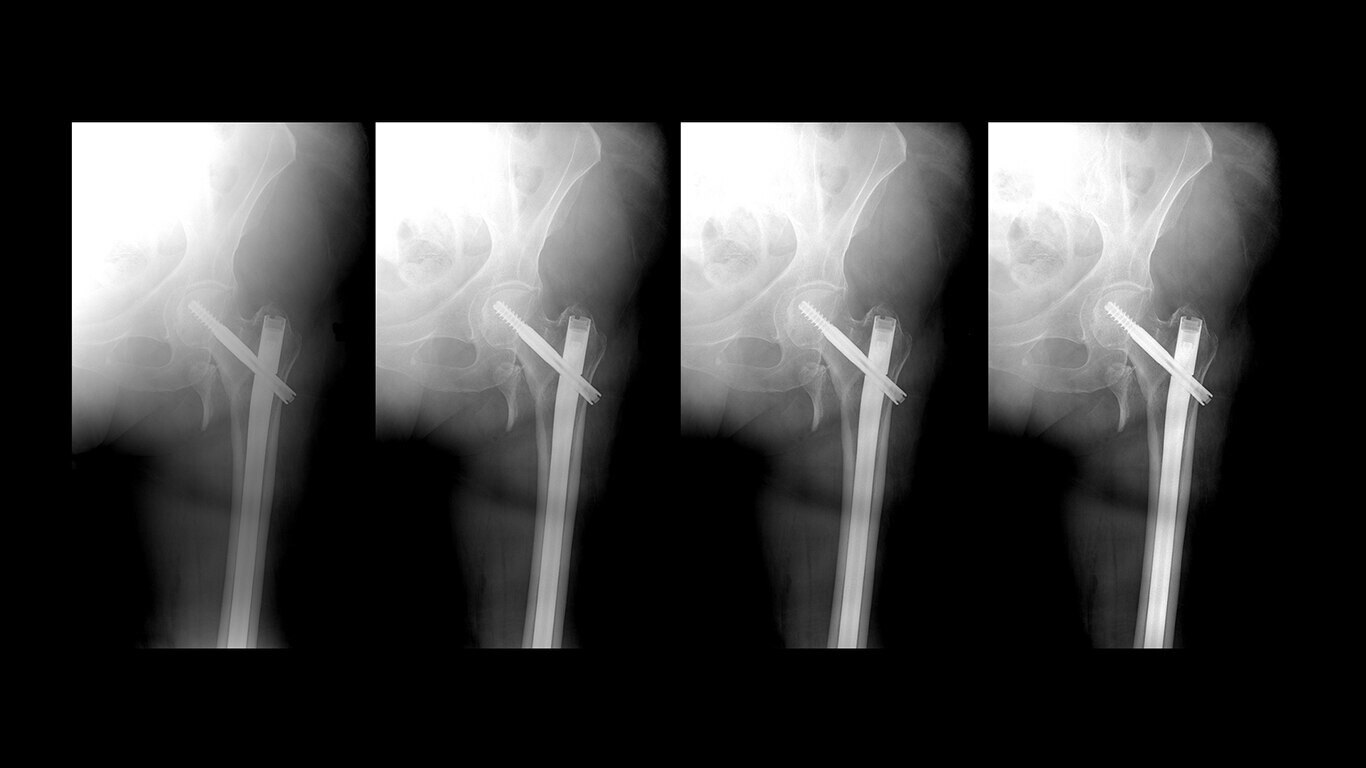

Uncompromised image quality

Capture high-resolution images with powerful, glassless detectors that weigh 40% less than previous generations3